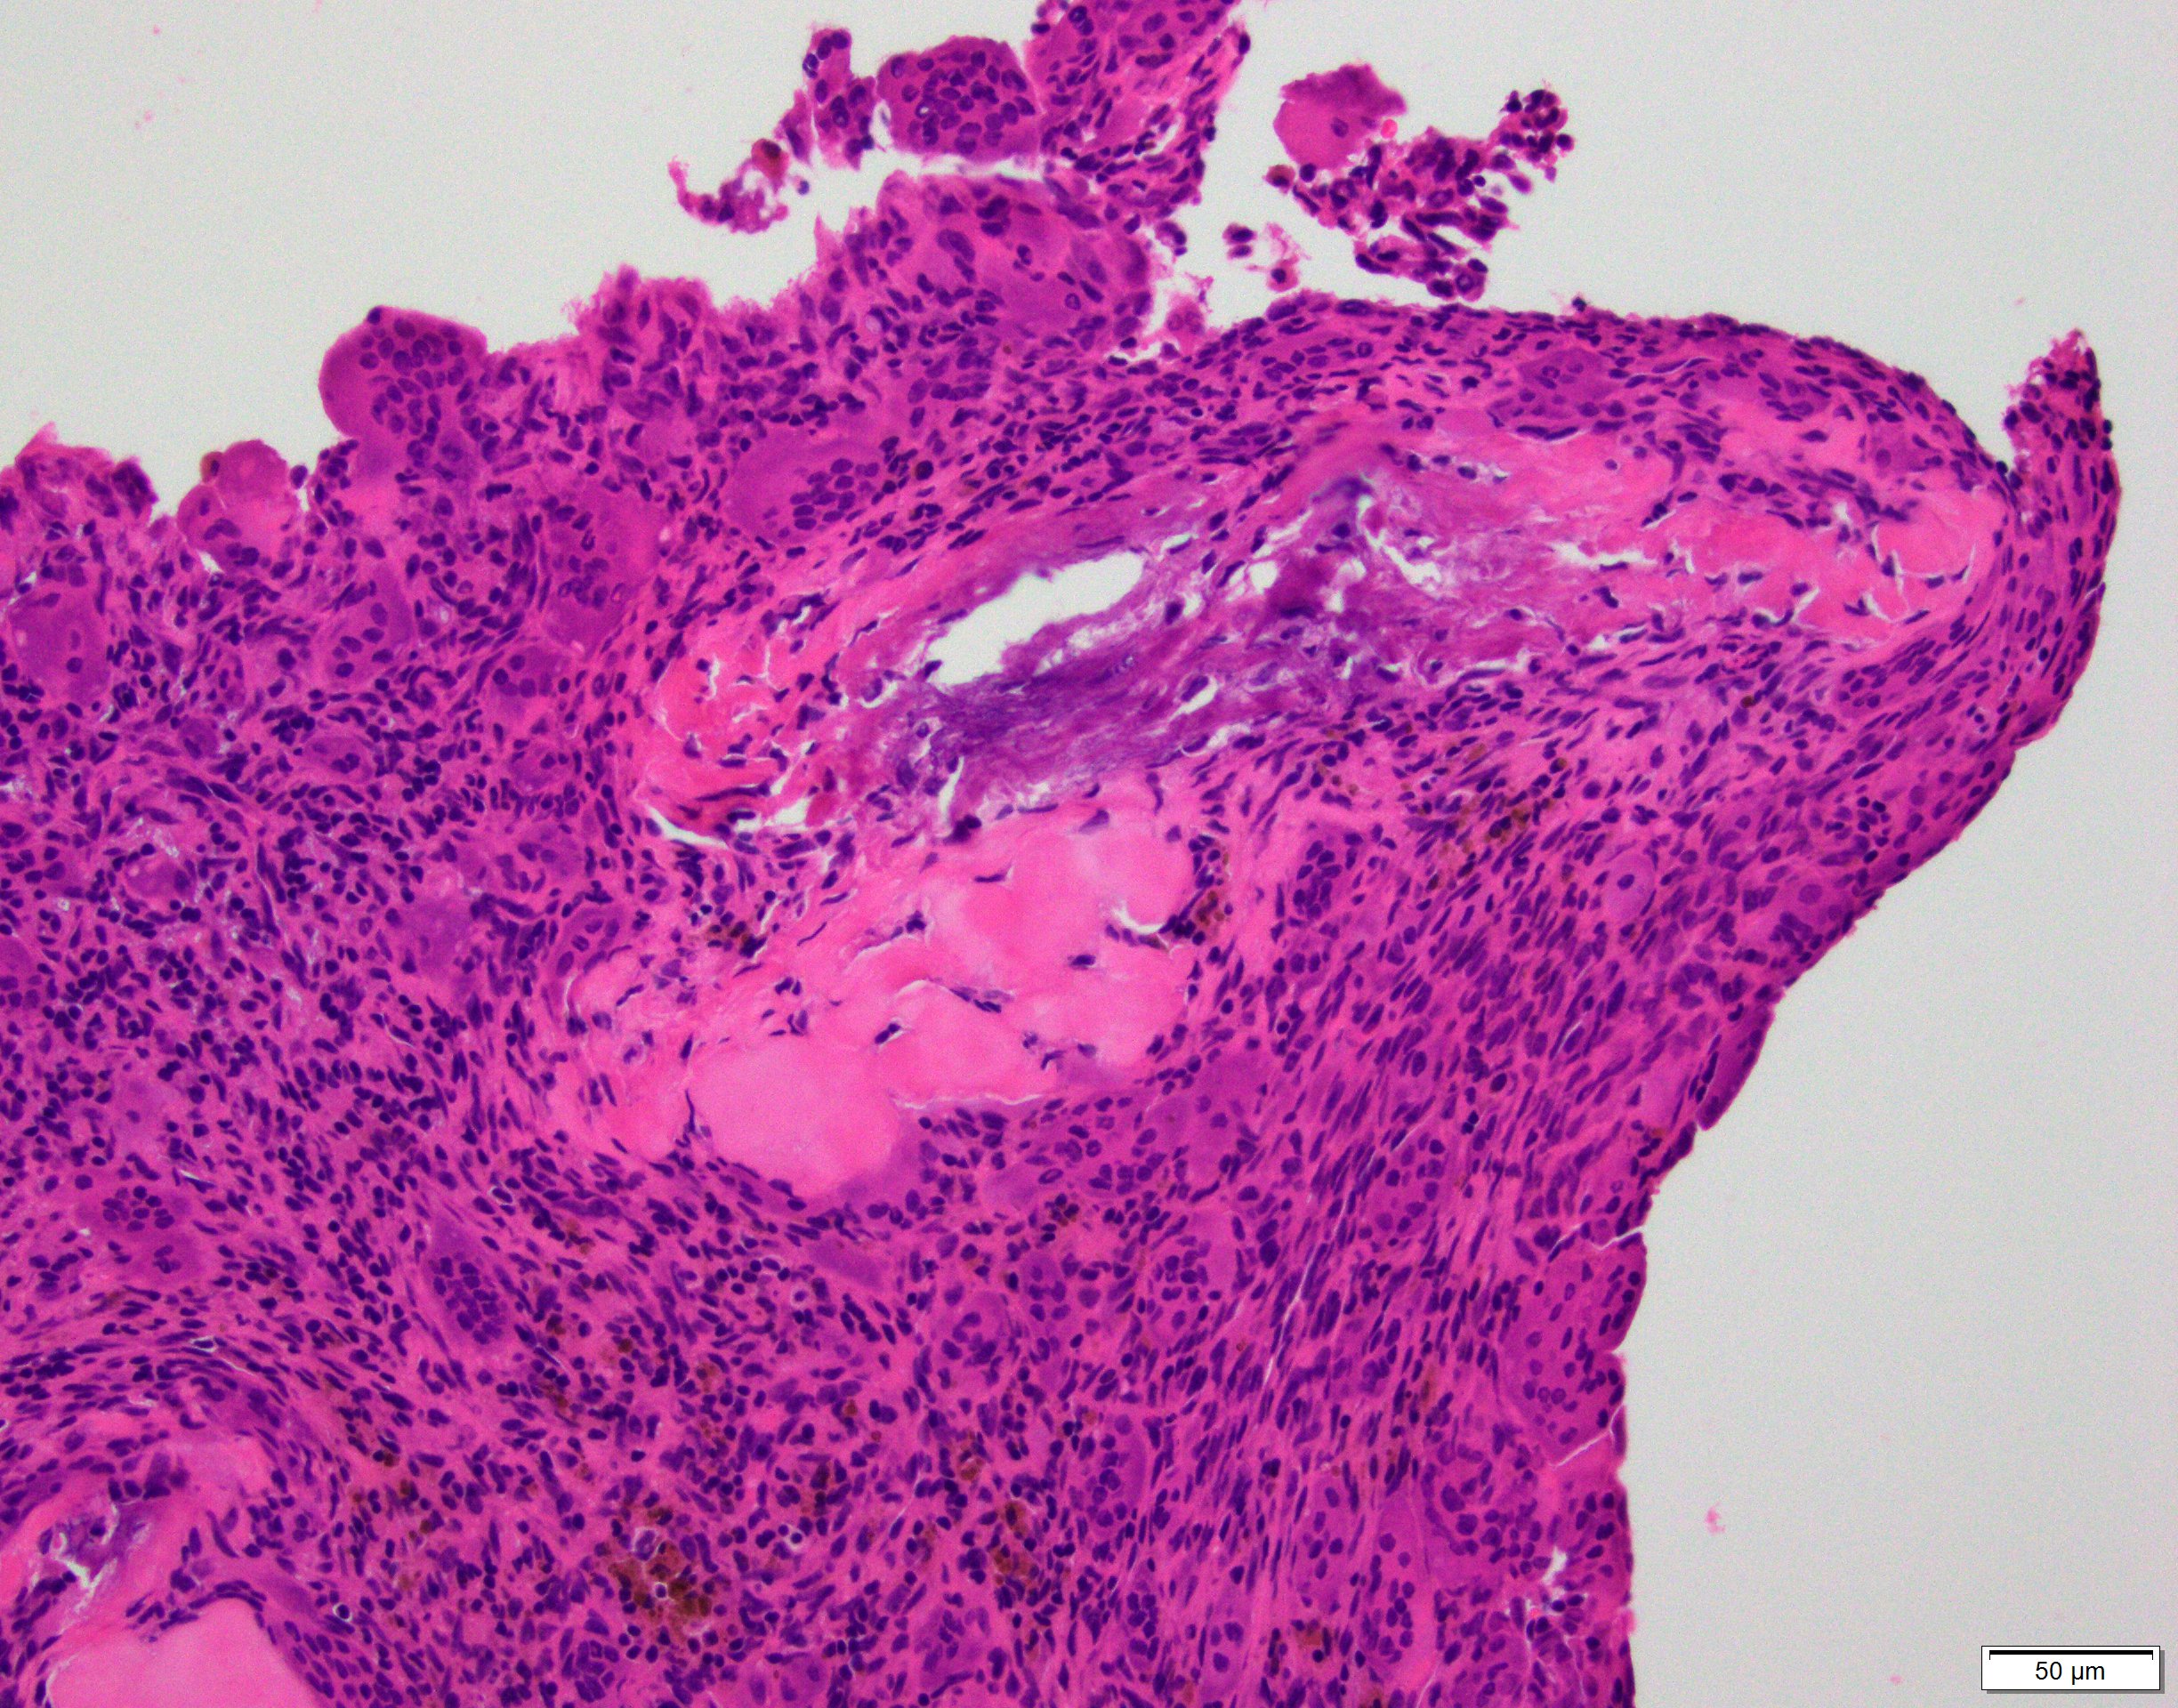

- Multiloculated cystic lesion

- Blood filled cystic spaces separated by cellular septa containing fibroblasts, giant cells and woven bone

- Calcified, basophilic material (blue reticulated chondroid-like material)

- Necrosis not common but mitotic activity is easily identified

- No cytologic atypia (Am J Clin Pathol 2015;143:823)

- Numerous giant cells in connective tissue that line large sinusoidal spaces

Microscopic (histologic) images

Contributed by Elham Nasri, M.D. and Kelly Magliocca, D.D.S., M.P.H.

A. Aneurysmal bone cyst. The H&E shows cystic spaces with stromal giant cells. Rearrangement of USP6 gene confirms the diagnosis in the above clinical and radiographic context.